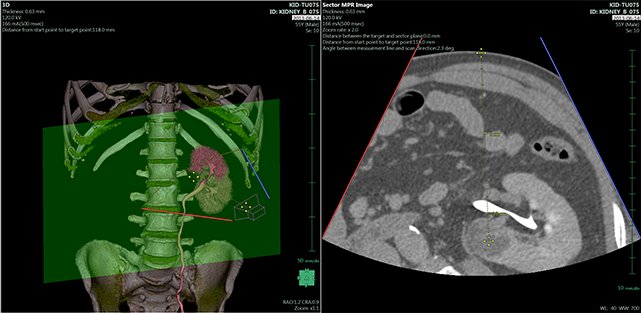

View X-Ray CT & MRI Scans Fast and Easily

Designed for surgeons, Pro Surgical 3D makes it easy to view patient scans quickly. Pro Surgical 3D facilitates the optimal 3D treatment and assessment workflows based on X-ray CT and MRI scans – and best of all, it’s FREE!

Traditional multi-planar slicing

High-quality and fast 3D reconstruction and 3D rendering

Performs 3D reconstruction and volume rendering.

Multi-planar slicing.

Oblique slicing.